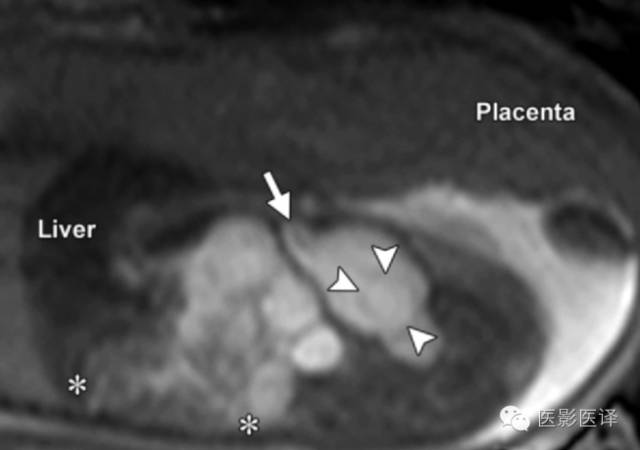

图8MR图像可清晰显示胎儿解剖。(a)稳态进动MR图像矢状位显示一囊肿内伴多发分隔(黑箭),该囊肿位于肝脏下缘、肾脏(K)前缘。可见脐静脉(uv;白箭)进入肝左叶。(b,c)稳态进动MR图像横断位显示胎儿子宫(图b中箭头所示)位于膀胱(B)后方,提示女性内生殖器,阴唇(图c中箭头所示),提示女性外生殖器。证实了女性生殖器存在也就可以支持卵巢囊肿的诊断;若显示为男性生殖器则可以将卵巢囊肿从鉴别诊断中排除。